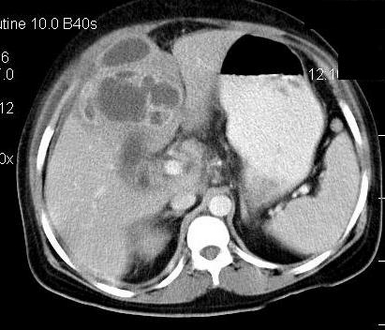

An empyema (/ˌɛmpˈmə/) is a collection of pus within a naturally existing anatomical cavity. For example, pleural empyema is empyema of the pleural cavity. It must be differentiated from an abscess, which is a collection of pus in a newly formed cavity. The term is from Greek ἐμπύημα, "abscess".

Gallbladder[edit | edit source]